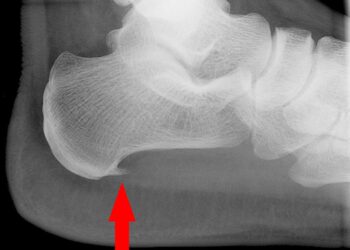

Read moreDetailsHielenpohjassa kovettumista kokeneet ihmiset tietävät, kuinka kivulias tämä vaiva usein on. Vaikka kantaluupiikki esiintyy useammin yli 40-vuotiailla, voi se ilmetä...